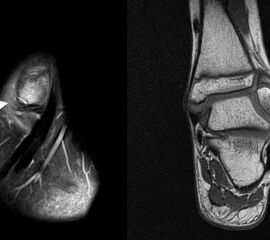

Os subfibulare

Multiple laminäre Ausrisse des fibularen Bandapparats aus der Fibulaspitze können zur Entwicklung eines Os subfibulare führen. Das Os subfibulare findet sich unterhalb der Fibulaspitze ventral der Peronealsehnen. Ohne Schmerzsymptomatik bzw. Aktivierung im MRT hat Das Os subfibulare keinen Krankheitswert. Ein mobiles Os subfibulare führt zu einer lokalen mechanischen Reizung teilweise in Verbindung mit einer Instabilität des Sprunggelenks. Im MRT zeigt sich eine Aktivierung des instabilen Areals. Bei anhaltenden Schmerzen besteht die Behandlung in einer operativen Entfernung des Knochens mit Refixation des Kapselbandapparats.

Os trigonum

Das Os trigonum lässt sich als isolierter Knochen dorsal des Talus seitlichen Röntgenbild darstellen. Normalerweise hat das Os trigonum keine klinische Relevanz. Bei entsprechenden Beschwerden und einer Aktivierung im MRT kann der Knochen arthroskopisch entfernt werden. Gehäuft beobachten wir eine mechanische Problematik durch das Os trigonum bei jugendlichen Fußballspielern und Tänzerinnen.